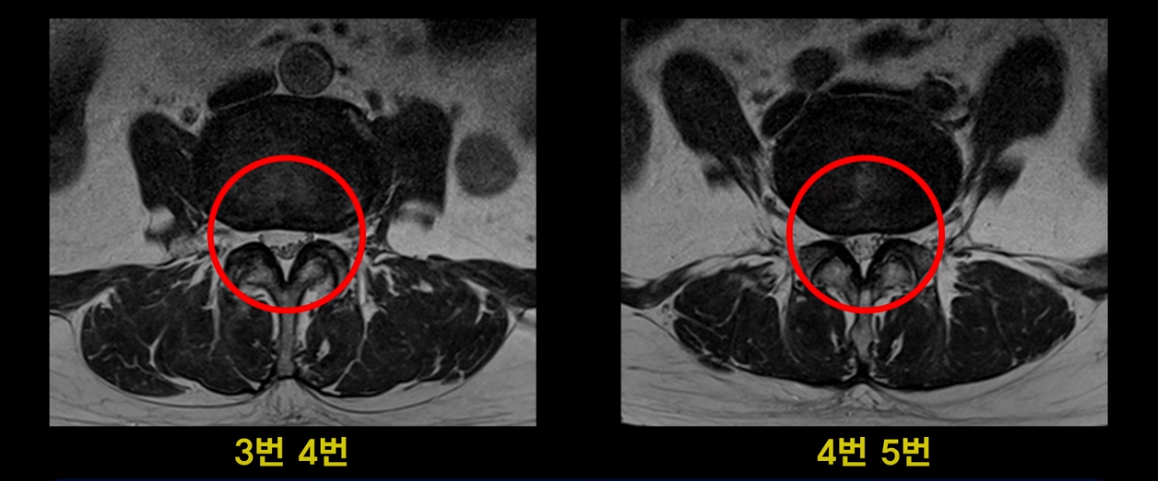

이분 MRI를 보면 여러 마디가 퇴행이 진행되어 있고

3번 4번과 4번 5번에 중심성 협착이 있는데

4번 5번이 더 심합니다.

또 4번 5번 마디에 오른쪽으로 찢어져서 밀려나온 디스크 탈출이 보입니다.